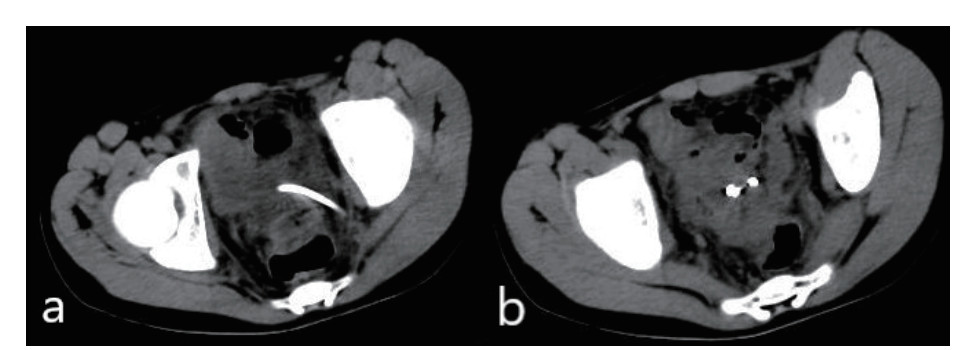

患者入院后完善相关检查,血常规:白细胞6.73×109/L,中性粒细胞4.87×109/L,血小板126×109/L;C-反应蛋白 > 90 mg/L;降钙素原7.6 ng/mL;凝血功能:PT 15 s。盆腔超声显示:骶前间隙可见一80 mm×46 mm的无回声区,内可见斑点样中强回声(图 2)。排除禁忌后,于入院当晚行超声引导下穿刺置管引流术,由于脓肿位置较深,经腹途径有肠管﹑膀胱和直肠的遮挡,所以本中心决定选择超声引导下经臀穿刺引流术。

| 图 2 盆腔超声显示:骶前间隙可见一80 mm×46 mm的无回声区,内可见斑点样中强回声 |